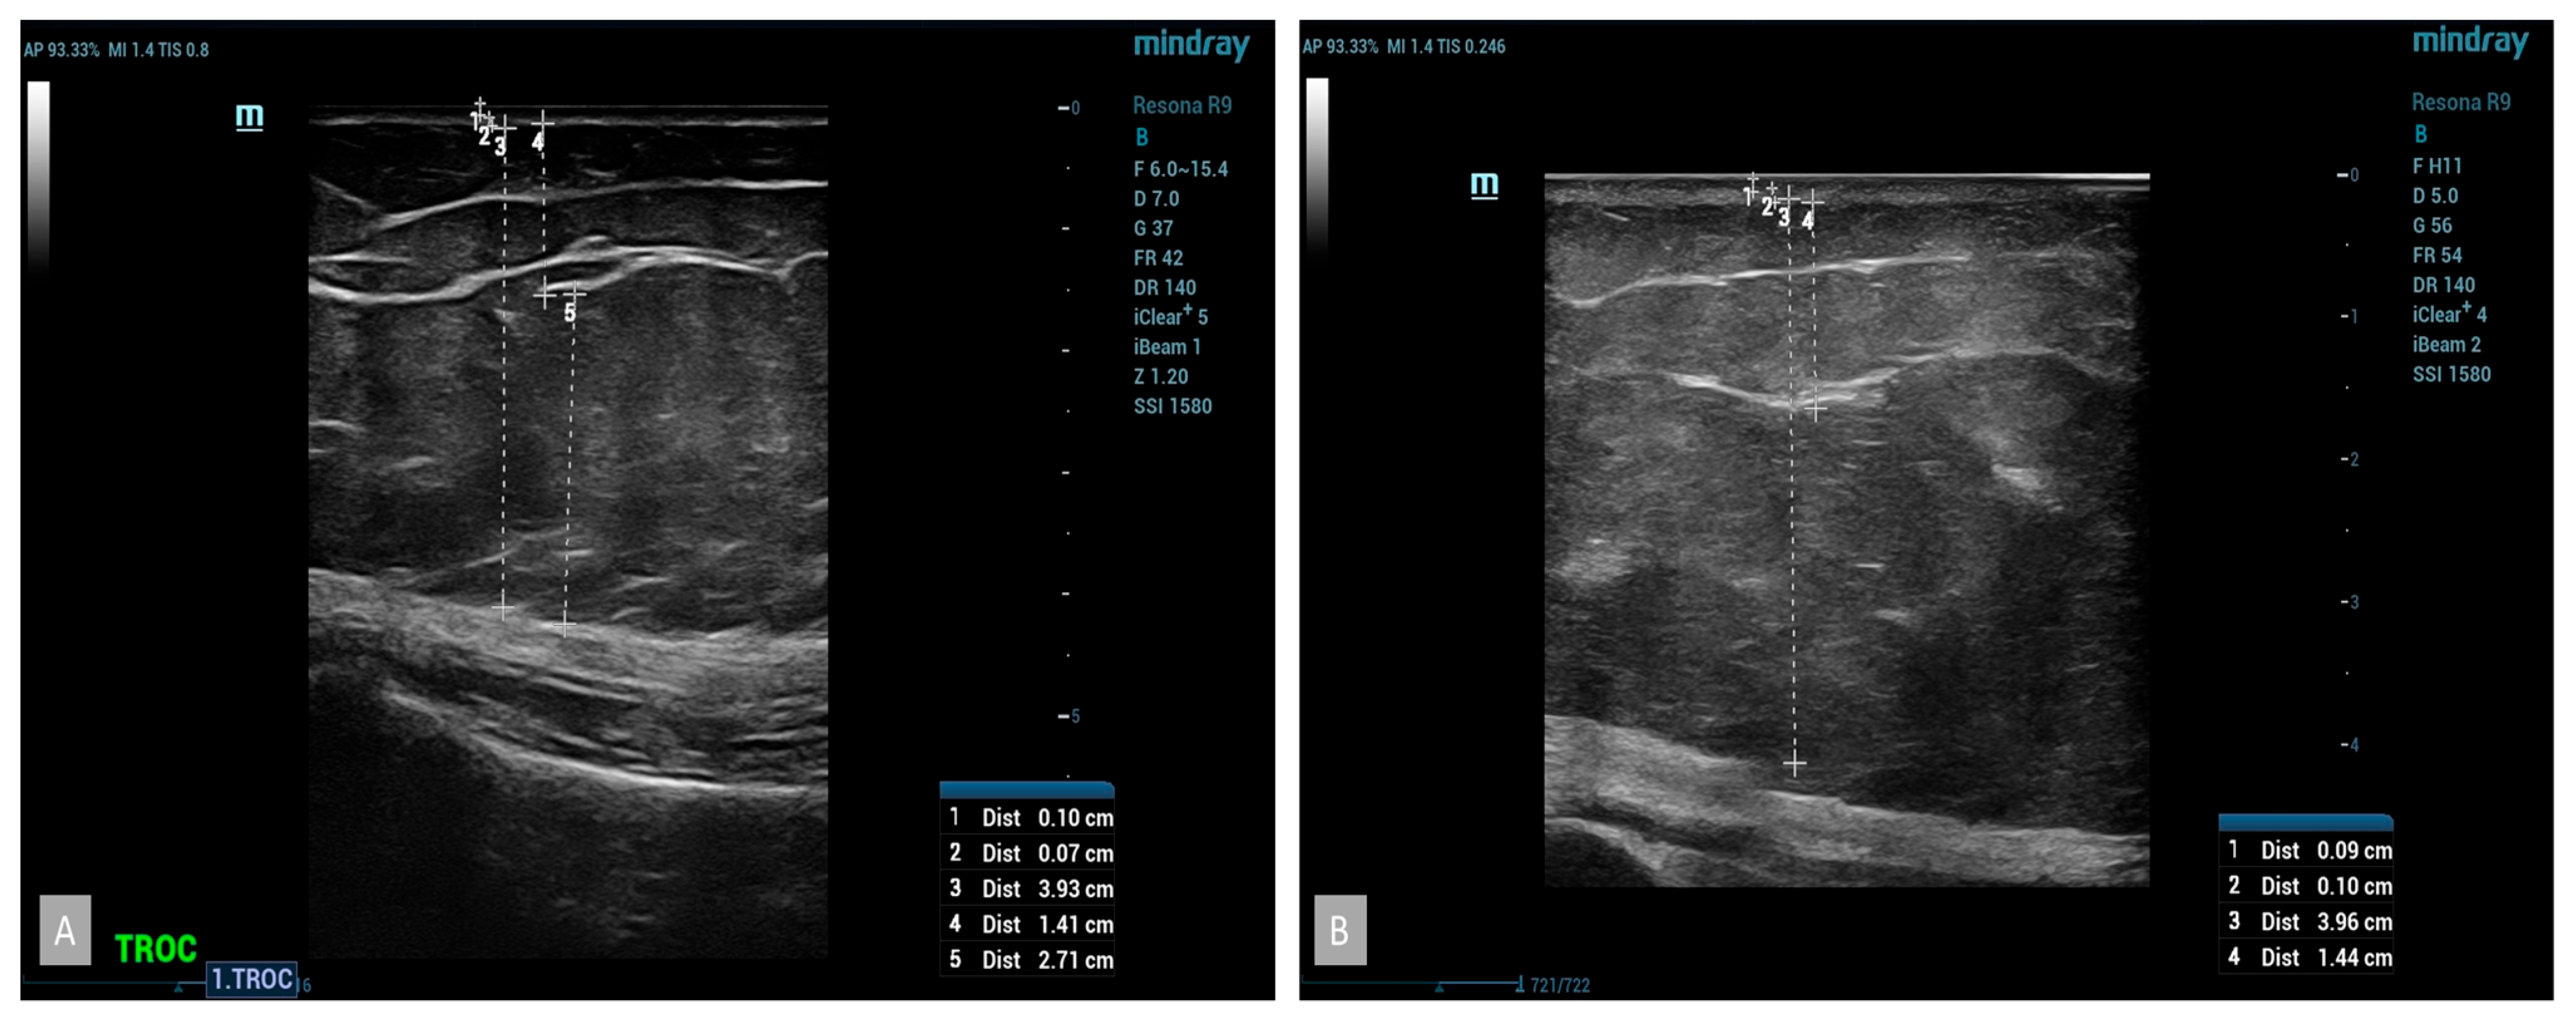

B-mode ultrasound examinations revealed significant changes in the parameters studied. The thickness of the subcutaneous tissue was reduced, confirmed by the results obtained from measuring the circumference of the thigh (Figure 4). The average reduction in the thickness of the subcutaneous tissue in the group using cellulite cream was 2 mm after 42 days and 3 mm after 84 days of treatment. No statistically significant changes were noticed in the placebo group (Figure 5). The analysis of the thickness of the dermis showed that, following the anti-cellulite treatment used, no substantial changes were found. Similarly to the case of the thickness of the subcutaneous tissue, no significant differences were noted in women taking the placebo. As for the thickness of the epidermis after the completion of treatment, no differences were observed in both the hypertonic cream group and the placebo group before and after the completion of treatment. The comparison of echogenicity before and after anti-cellulite treatment showed an improvement in subcutaneous tissue echogenicity in 25% of the patients with hypertonic cream according to the index of reduction of edema of subcutaneous tissue. In the placebo group, the echogenicity did not change. In addition, the analysis of vascular-connective shoots showed that in cases of moderate–severe cellulite (grade II or III according to the Nürnberger–Müller scale), the latter showed an irregular and discontinuous trend, and after the application of the device, there was an improvement in the regularity of the same in 20% of the hypertonic cream group. No significant differences were noted in women taking the placebo. The additional color-doppler US examination showed that 53% of patients showed abnormalities in the venous system of the lower limbs, particularly regarding the presence of perforating veins such as Cockett B in 25% of patients, Boyd in 15% of patients, and Huxley in 1% of patients.

Figure 5. Placebo, at baseline US, pre (A) and post treatment (B) evaluation of placebo patient did not show any significant changes.